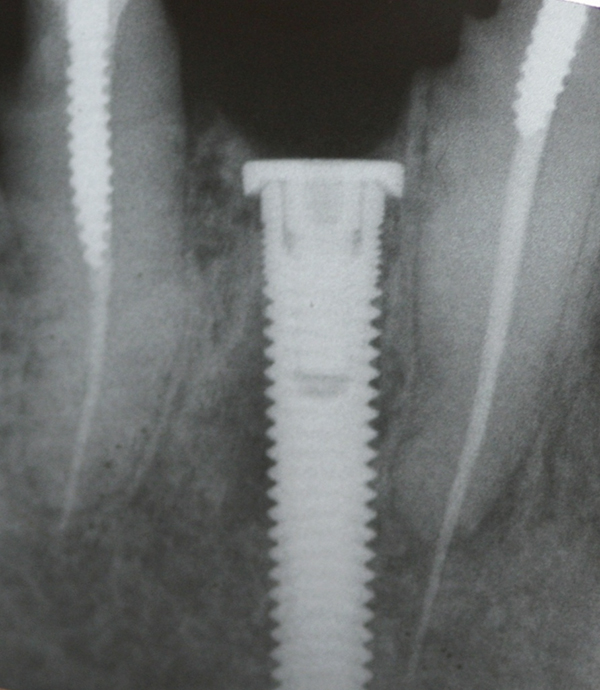

Fig 3. Examples of implants with different thread designs. On the left is an implant with standard v-threads, and on the right is an implant with larger, more aggressive threads. The implant on the right was inserted with 20-Ncm-greater insertion torque than its counterpart.

Figure 3

Subsequently, Trisi et al2 confirmed that increased insertion torque reduced implant micromotion when the implants were subjected to lateral forces in vitro (bovine bone). However, it was noted that this relationship may not always be true for all implant designs (Figure 3) and drilling techniques.61 For instance, compared with soft bone, there may be no benefit in increasing insertion torque in dense bone after stability is attained. One can surmise that a moderate increase of insertion torque may provide some benefits with respect to reducing micromotion, especially in less dense bone. However, the amount of increased force that is beneficial is unclear. Another technique to enhance initial stability is to use tapered implants, which develop elevated insertion torque forces. 14,62